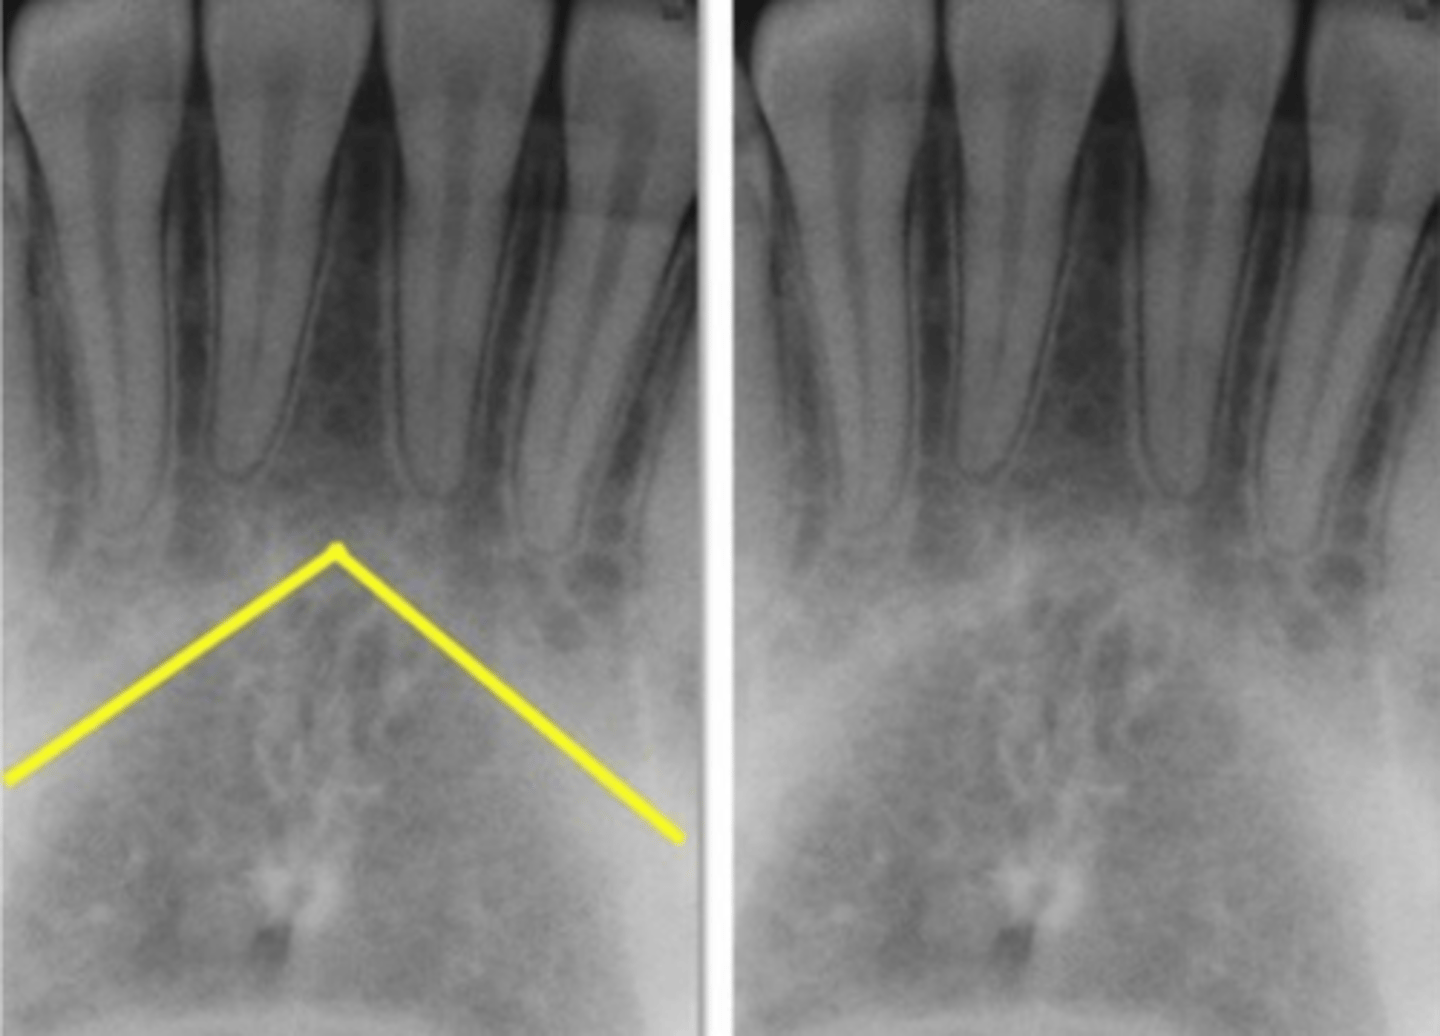

yellow line- zygomatic process

white arrow - zygomatic bone

Identify the two structures

<p>Identify the two structures</p>

Zygoma

Name the horizontal radiopaque line labeled #2.

Floor of maxillary sinus

Name the curved line scalloping between tooth roots labeled #3.

Mental ridge

What makes the inverted-V shaped line indicated?

<p>What makes the inverted-V shaped line indicated?</p>